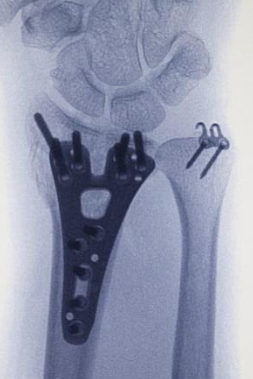

Konservatif tedavinin uygun olmadığı durumlarda cerrahi tespit önerilebilir. Distal radiusun sabitlenmesinde artık en yaygın yaklaşım, bileğin volar yönündendir. Bu, anatomik volar kilitleme plakasının kullanılmasını gerektirir. Birçok avantajı arasında daha az fark edilen bir cerrahi yara izi yer alır; kilitleme vidalı titanyum plaka daha iyi stabilite sağlar ve özellikle osteoporotik kemikleri olan hastalar için endikedir. Ulnar stiloid tabanda kırılmışsa kırığın onarılması tavsiye edilir.

Cerrahlar, kemik iyileşirken kırık kemiği doğru pozisyonda tutmak için birkaç alternatife sahiptir :